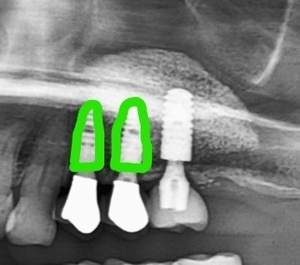

当時、左上45(緑色)が歯周病により抜歯。

骨の高さが少ないため、サイナスリフト後にインプラントを2本埋入。

左上6(オレンジ)は、まだ、しばらくご自身の歯が使えてましたが、抜歯後のことも考えて増骨(サイナスリフト)は

3本分をまとめて行いました。

左上6が抜歯になっても、増骨が出来ているので、すぐインプラントが埋入できます。